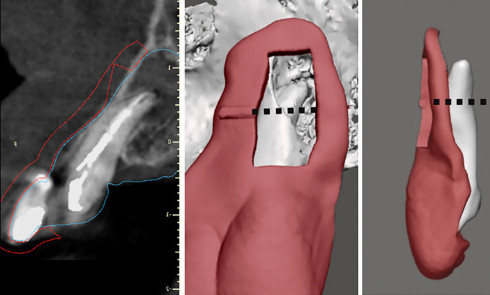

La compréhension de ces instruments, des biomatériaux et des différentes techniques est essentielle, et doit nous guider dans nos prises de décision en fonction des situations cliniques. Dans le cas clinique présent, suivi sur 24 mois, le patient se présente avec des douleurs à la mastication sur la dent 36. Tous les signes cliniques (test au froid négatif, test à la percussion positif, sondage parodontal positif en vestibulo-distal avec présence de fistule) et les examens radiologiques (LIPOE sur la racine distale, lésion inter-radiculaire) convergent vers un diagnostic de nécrose pulpaire due à une fracture longitudinale non complète (type 3 : Classification AAD) [1] (fig. 1).

La mise en forme doit également s’adapter aux singularités anatomiques. Pour ce cas clinique, le canal mésio-lingual a été mis en forme en premier jusqu’à la longueur de travail. Puis le test du cône a été réalisé (fig. 4 et 5) afin de voir si les deux canaux se rejoignaient. Ces deux canaux se rejoignant à 3 mm de l’apex, le canal mésio-vestibulaire a été mis en forme à sa longueur de travail moins 3 mm afin d’éviter la zone de confluence et le risque accru de fracturer un instrument. De plus, cette mise en forme longueur de travail-3 mm a son importance pour la précision de l’obturation et l’ajustage des cônes. Pour le canal distal, qui était un canal « en 8 », nous appliquons le même raisonnement que pour les canaux mésiaux, avec un canal principal, test du cône, et ajustage des maîtres-cônes (fig. 6).